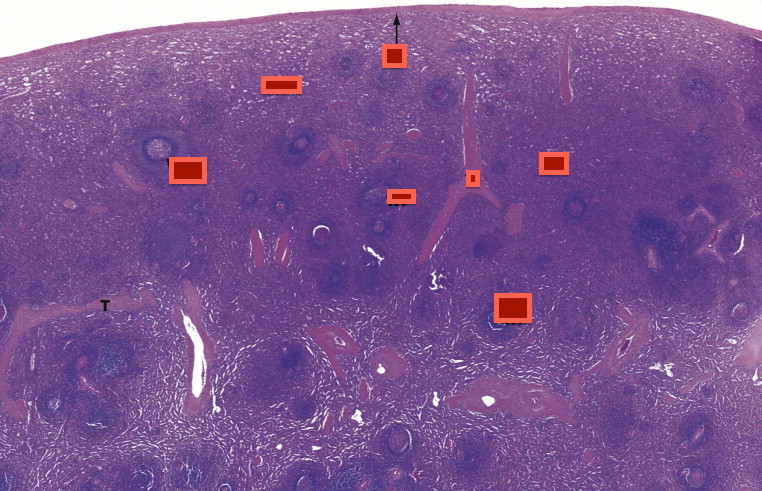

Thymus, cortex, medulla

Name the structures

Spleen

White Pulp

Red Pulp

MALT

mucosa associated lymphoid tissue